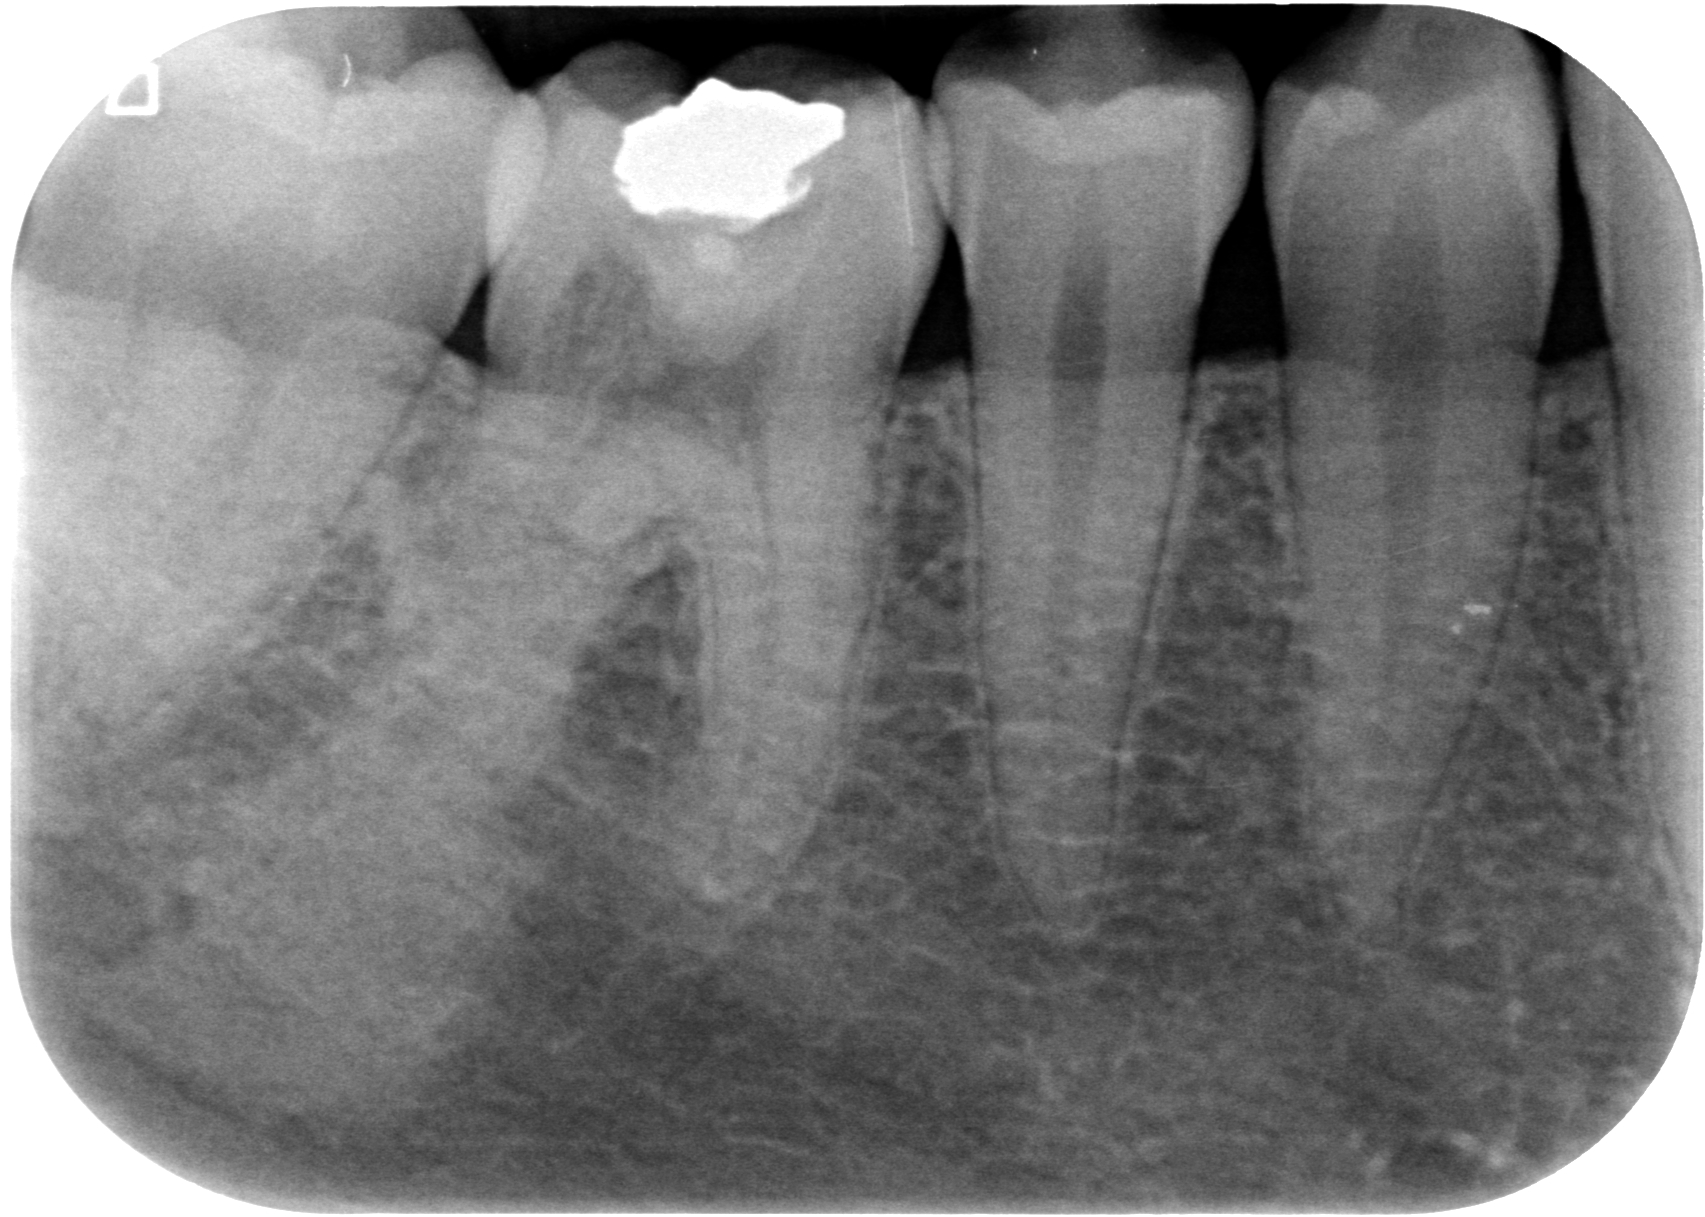

Sì, perchè ora faccio il figo, ma nel non lontano 2011, mi arriva una paziente con questo dente.

E questa è stata la mia reazione.

Cosa caspita era capitato a questo dente? Allarmato faccio vedere la radiografia a Federico, il mio socio, e anche lui pensa a qualcosa di brutto. Che so, un tumore di quelli incomprensibili che avevamo studiato solo sui libri di radiologia che si era insinuato all’interno di questo 4.6! ???

Quando nel 2013 mi è arrivato all’attenzione questo caso

Ho riconosciuto lo stesso fenomeno visto nella ragazza infestata da tessuti alieni di cui sopra e mi sono ricordato che all’università si era parlato di riassorbimenti esterni.

Si trattava di un riassorbimento esterno di classe IV.